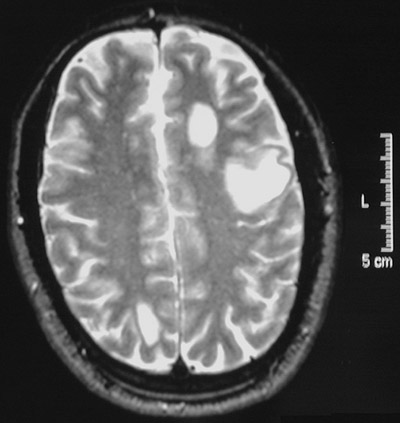

| The three much larger bright plaques of demyelination are seen here with a T2 weighted MRI scan in axial view above and an axial FLAIR scan below. This is a patient with an exacerbation of multiple sclerosis. A single large plaque may mimic a tumor mass. |